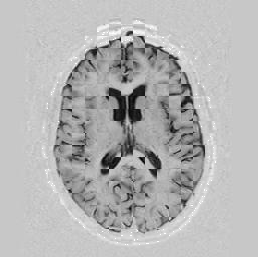

Another larger group of experiments enabled me to study the effects of multi-scale NRR. The results are shown in the form of chequerboard images in Figure [*]. In terms of resolution levels, higher numbers mean that the images are coarser.

Judging by some later stages when resolution is increased, the conclusion reached is that the added computational effort, which is enormous, makes this increase unneeded. The increase in resolution does not reveal much new information about the image structure, at least not at the stage when registration is still far from being entirely approached.

Figure: Multi-scale NRR (increasing resolution). From left to right, top then bottom:before NRR; after 5 iterations of NRR at level 2 (higher is coarser); after another 5 iterations of NRR at level 1.